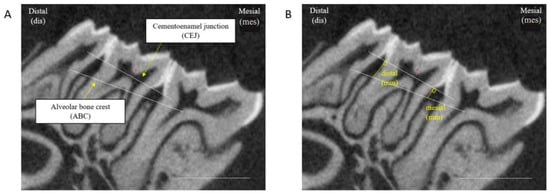

2.10. Measurements of Alveolar Bone Loss

2.10.1. Micro-CT Tomography

2.10.2. Measurement of Alveolar Bone Loss